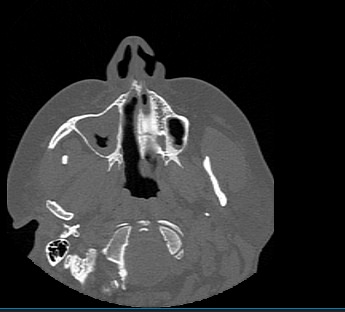

Одним из методов диагностики заболеваний носоглоточной области является мультиспиральная компьютерная томография. КТ носоглотки назначают при подозрении на рост новообразований, в случае хронического воспаления, при врожденных аномалиях строения носа и прилегающих к нему придаточных пазух.

Методика предусматривает использование рентгеновского излучения. Благодаря различной способности тканей поглощать рентгеновские лучи и последующей цифровой обработке полученных данных, удается получить изображения исследуемой зоны в мельчайших подробностях.

В медицинских центрах «Доступная медицина» сканирование носоглотки выполняется на современных мультиспиральных компьютерных томографах экспертного класса TOSHIBA AQUILION. Модификации данных аппаратов снабжены увеличенным количеством высокочувствительных детекторов, которые производят послойное сканирование, делая одномоментно от 64 до 128 срезов анатомической зоны. Это позволяет проводить исследование за несколько секунд. Такая быстрота выполнения исследования обеспечивает минимальную дозу рентгеновского облучения для пациента.

Инновационные цифровые приложения томографов позволяют получить снимки высокого качества и детализации, а также создать трехмерные реконструкции анатомической зоны исследования, что дает возможность рассмотреть пространственное расположение органов и патологических образований.

Мультиспиральная компьютерная томография позволяет выявить практически все заболевания ЛОР-органов и, в частности, носоглоточной области. С помощью КТ носоглотки можно диагностировать:

- острые и хронические воспалительные заболевания носоглотки, включая аденоидит (воспаление носоглоточных миндалин);

- аденоиды, кисты, полипы носоглотки;

- доброкачественные и злокачественные опухоли носоглотки, придаточных пазух носа, костей лицевого черепа с определением их размеров и точной локализации, поражение регионарных лимфоузлов;

- инородное тело носа, носоглотки, гортани;

- посттравматические изменения;

- аномалии развития носовой перегородки и области носоглотки.